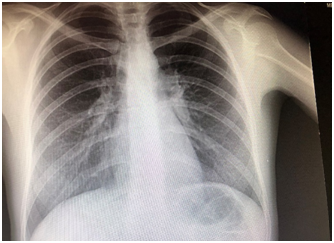

A 30 year old woman was admitted for dry cough, polyarthralgia, and subfebrile fever that developed following two weeks of amoxicillin-clavulanate treatment for maxillary sinusitis. Her past medical history was remarkable. The family history did not reveal any disease of medical interest. Four weeks before admission the patient developed fever (38.4°C), postnasal purulent discharge, and maxillary pain. WBC was 13.2×103/ml with 79 percent neutrophils, CRP: 55.5, ERS: 48mm/h. The patient was commenced on amoxicillin clavulanate 1000mg bid for fourteen days. Dry cough, dyspnea on exertion, polyarthralgia, and fever occured three weeks after amoxicillin clavulanate treatment. Chest x-ray was normal (Figure 1). Blood biochemistry was within normal limits. There was no radiologic abnormalitiy on joint films. Arterial blood gases; pH: 7.39, pO2: 84.2, and pCO2: 38.6mm Hg. ECG revealed sinus rhytm (84/min). Tuberculin test was negative. Chest CT showed bilateral multiple subpleural nodules in the lingula (one; 3mm), left lower lobe (multiple; 1-2mm), right lobe anterior segment (two; 5mm and 15X10mm) (Figure 2). Serum ACE was 24U/L. Sputum smear and culture were negative for bacteria, mycobacteria, and fungus.

Figure 1 Normalinitial chest x-ray.